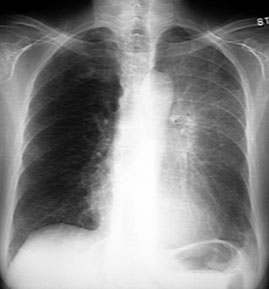

Resorptive Atelectasis of LUL

Cancer Lung

LUL atelectasis due to endobronchial obstruction. Once the bronchus is obstructed, there is no ventilation and the air gets absorbed. The distal lung is now devoid of air and becomes atelectatic.

Black arrowhead pointing to atelectatic LUL.

Signs of loss of lung volume:

Trachea (yellow arrow) is shifted to left.

White arrow is pointing to the bowing left oblique fissure. The fissure has moved forwards due to loss of LUL lung volume.